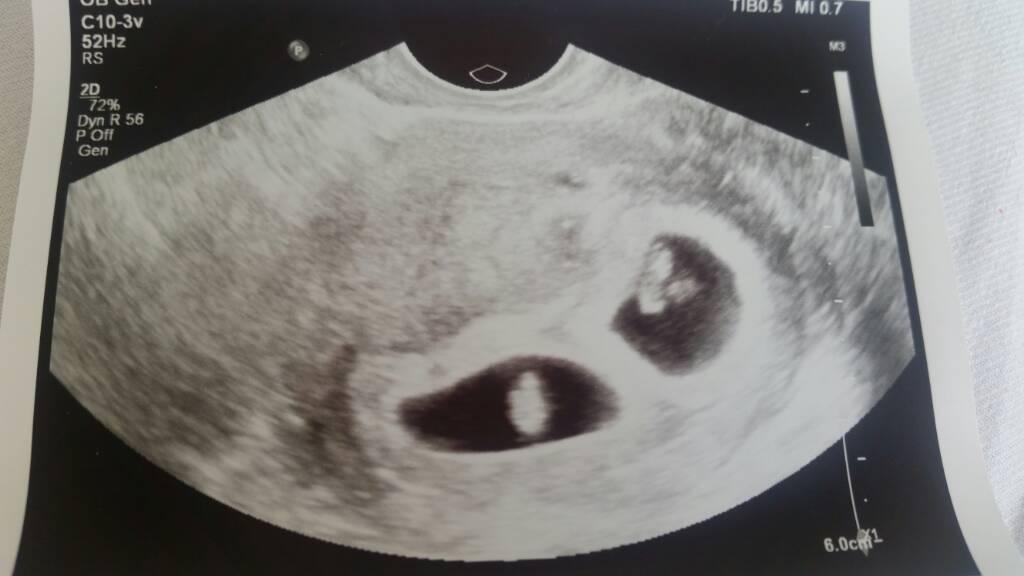

Odpoczywaj , odpoczywaj i jeszcze raz odpoczywaj .! Wszystko bedzie dobrze!Krwiak urosldzieci zywe, sa dwukosmowkowe i dwuowodniowe. Ale ciaza zywq, a ja leze w szpitalu i tylko do lazienki mozna mi isc.

A to moje maluszki